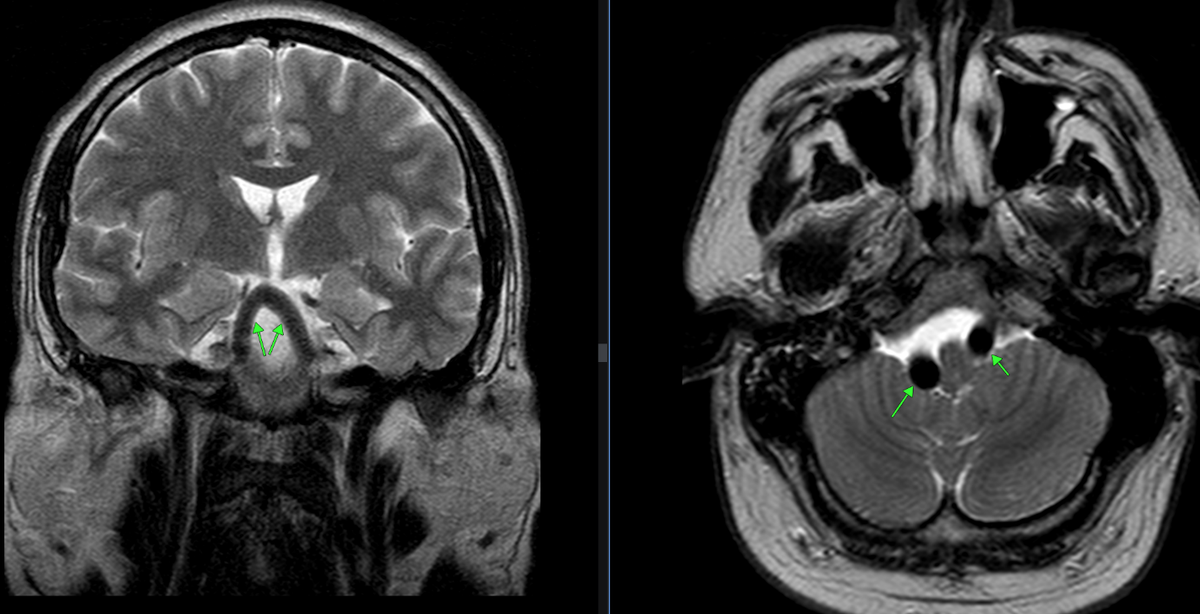

Рис. 1. Определяется выраженное расширение интракраниальных отделов позвоночных артерий, диаметром справа до 10 мм, слева до 8-9 мм (норма до 3.8 мм), с компримированием ствола мозга.

При проведении исследования были выявлены следующие изменения: долихоэктазия  интракраниальных отделов позвоночных артерий